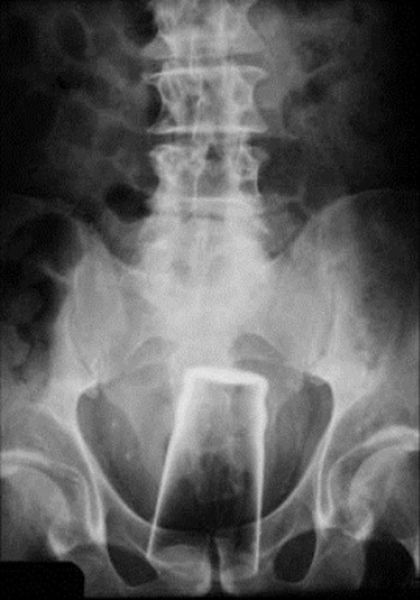

And the old classic: Pint Glass Up The Butt!

This X-ray reveals a cell phone lodged in a Salvadoran prisoner's lower intestine. The man is one of four prisoners who are members of the Mara Salvatrucha street gang. The men were caught with cell phones, spare chips and a charger that they had attempted to smuggle, according to authorities at San Salvador's Zacatecoluca prison.

This X-ray was taken of a 60-year-old man who checked himself into Nishtar Hospital in Multan, Pakistan. He sought treatment because he claimed thieves had inserted a Pepsi bottle into his anus before stealing two of his buffalo.

Getting a vibrator stuck in his bum wasn't enough to send this man to the ER. He simply attempted to remove the stuck object by using a pair of salad tongs. Trouble is, then the tongs got stuck, too!

This incident was not an accident, it was intentional. The late Ryan Dunn of the television show Jackass intentionally inserted a Matchbox car into his rectum just to mess with the ER doctors.

A Chinese man was complaining of stomach pains.The man, was forced to seek medical help after failing to extract a bottle with a curved piece of wire. When medical staff quizzed him on the pain, he claimed he did not know what was causing his discomfort.But he suddenly remembered what had happened when staff presented him with clear X-rays showing the bottle and wire inside of him. He admitted inserting the bottle at home before it became stuck and said he used a steel wire in an attempt to get it back out in a moment of panic.